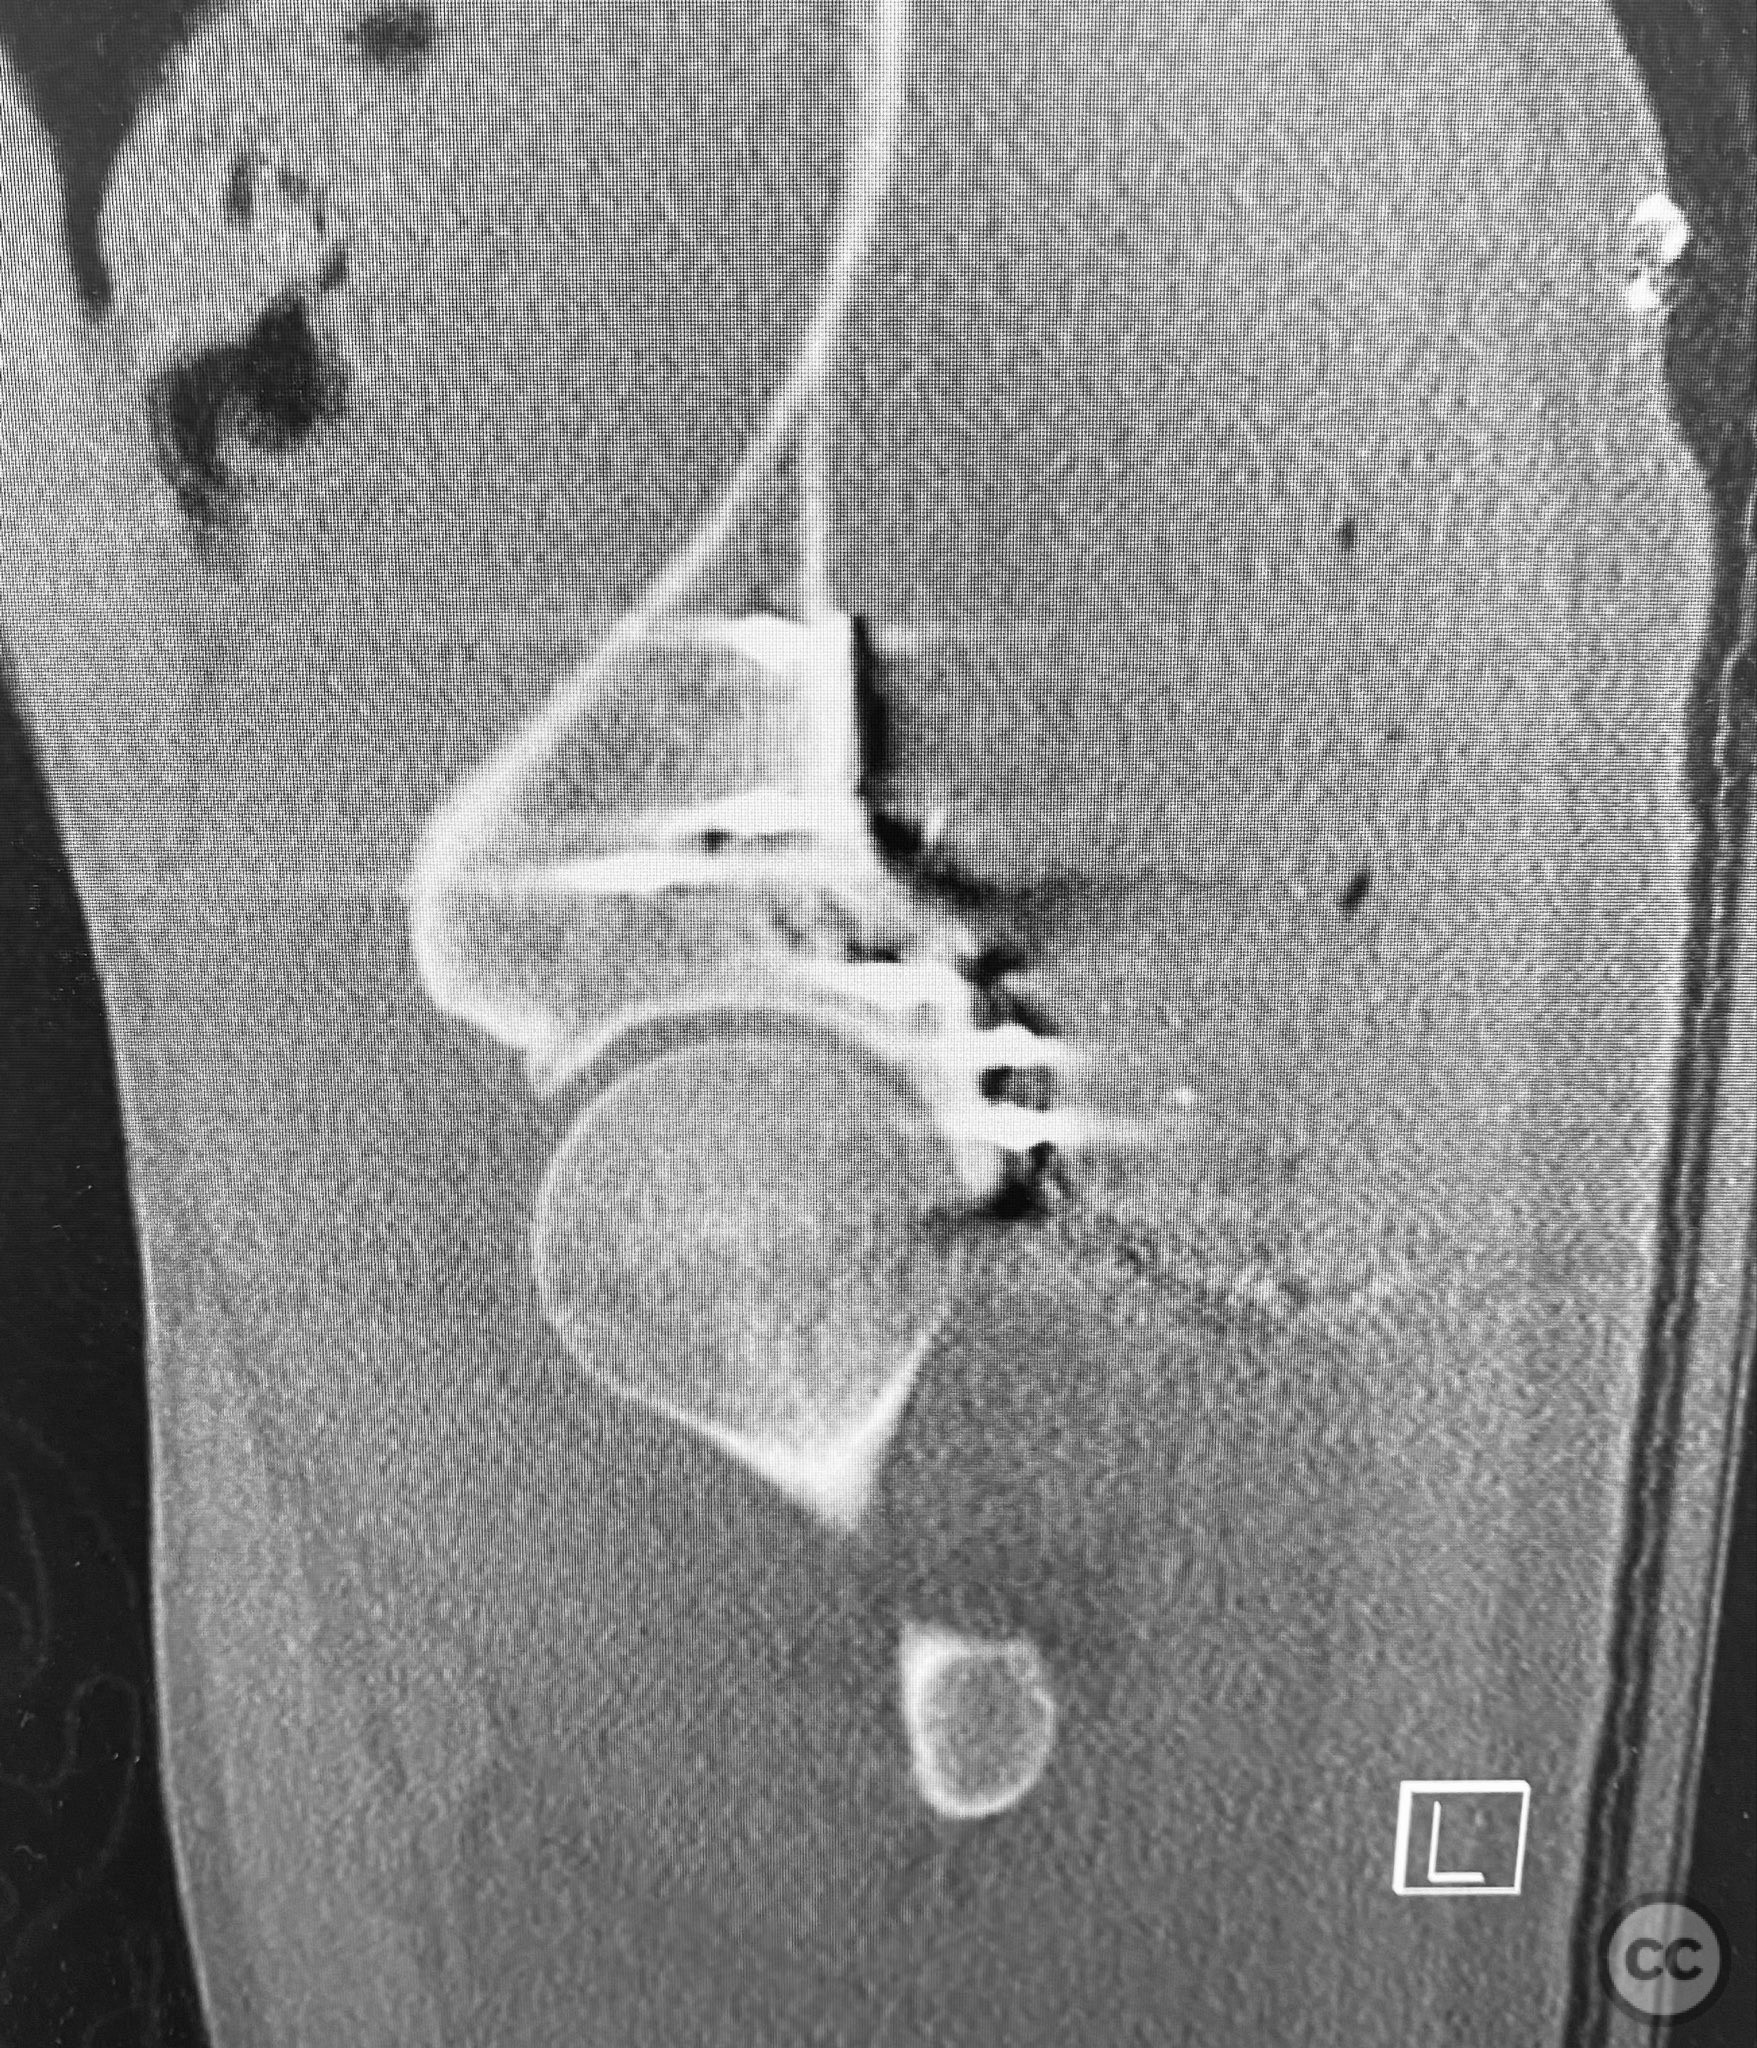

Anatomical surgical approach:  A standard Kocher-Langenbeck approach was utilized. A longitudinal incision was made centered over the greater trochanter, extending proximally and distally as required. The fascia lata was incised in line with the skin incision, and the gluteus maximus was split in the direction of its fibers. The short external rotators (piriformis, obturator internus, gemelli) were identified and retracted or released as necessary to expose the posterior column and wall of the acetabulum. The sciatic nerve was identified and protected throughout. The impacted articular surface was elevated using dedicated elevators, and the defect was filled with autologous corticocancellous bone graft harvested from the greater trochanter. The cranial wall fragment was reduced anatomically and secured with a spring hook plate. The main posterior wall fragment was then reduced and stabilized with a contoured reconstruction plate.

The initial failed closed reduction likely resulted from interposed soft tissue or bony fragments, or inadequate sedation/muscle relaxation. Repeat reduction under improved conditions was successful prior to definitive fixation. 3D CT renderings provided enhanced visualization of impaction zones and comminution, facilitating preoperative planning for grafting and fragment-specific fixation. Intraoperatively, elevation of the impacted dome required careful manipulation to avoid further chondral injury. Use of a spring hook plate provided secure fixation of the cranial wall fragment, while the reconstruction plate supported the main wall fragment. Postoperative CT confirmed satisfactory reduction and implant positioning.

Orthopaedic implants used:   Spring hook plate; 3.5mm reconstruction plate; autologous trochanteric bone graft; distal femoral K-wire (for skeletal traction)